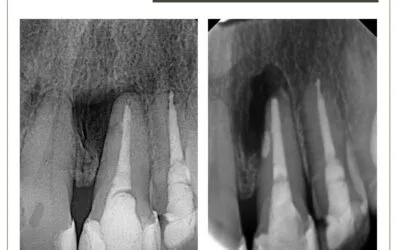

Reabsorção radicular cervical externa

Reabsorção radicular cervical externa. Paciente 30 anos, sexo feminino, com diagnóstico de reabsorção radicular...